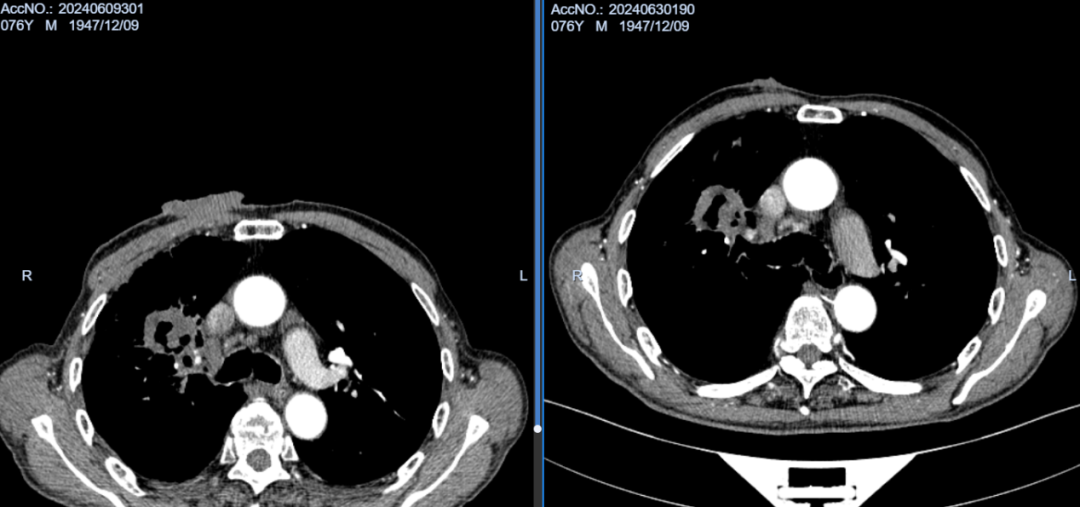

术后2月余,胸壁继发恶性肿瘤基本坏死,肺内原发病灶缩小明显,坏死空洞形成。

术后3月余,胸壁继发恶性肿瘤完全坏死,胸壁基本愈合,肺内病灶持续变小。